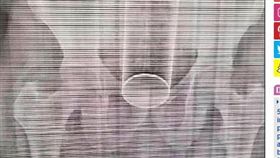

下體塞「空氣清新劑」 取不出GG了

多明尼加一名40歲男子和妻子做愛過程中,一時玩太嗨,...